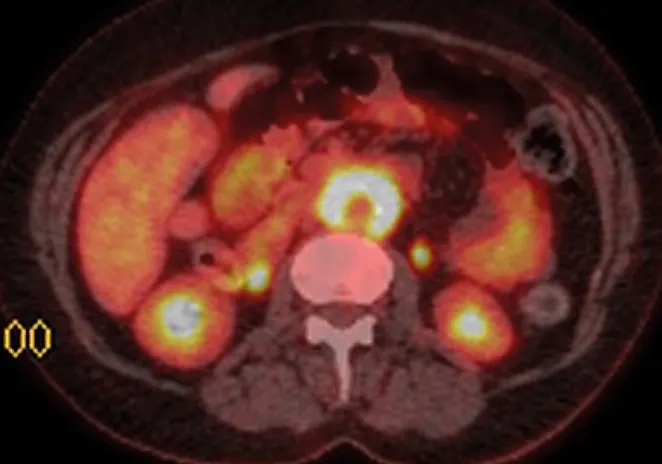

Традиционно для подтверждения диагноза ретроперитонеального фиброза применяется внутривенная урография, при которой могут быть выявлены длинные суженные участки мочеточника и его медиальное отклонение в проекции средней трети, а также гидронефроз. Тем не менее, при ретроперитонеальном фиброзе медиальное отклонение определяется не всегда, в то время как у 20 % людей с нормальными мочевыми путями также выявляется медиальное отклонение мочеточников. В последнее время для уточнения границ поражения при ретроперитонеальном фиброзе применяется компьютерная томография (КТ) и магнитно-резонансное исследование (МРИ), при которых выявляется объемное образование, окружающее полую вену и аорту.

Несмотря на то, что МРИ позволяет в некоторых случаях установить диагноз, радиографические методы исследования в настоящее время не дают возможность провести дифференциальную диагностику между злокачественными и доброкачественными причинами развития ретроперитонеального фиброза. Уточнить диагноз и провести дифференциальную диагностику между злокачественным и доброкачественным ретроперитонеальным фиброзом можно с помощью анализа множественных глубоких биопсий этого образования.